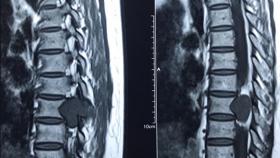

Nguyên nhân hẹp đốt sống và cách chữa hẹp đốt sống

Nguyên nhân hẹp cột sống và cách chữa hẹp cột sống

Nguyên nhân hẹp ống sống và cách chữa hẹp ống sống